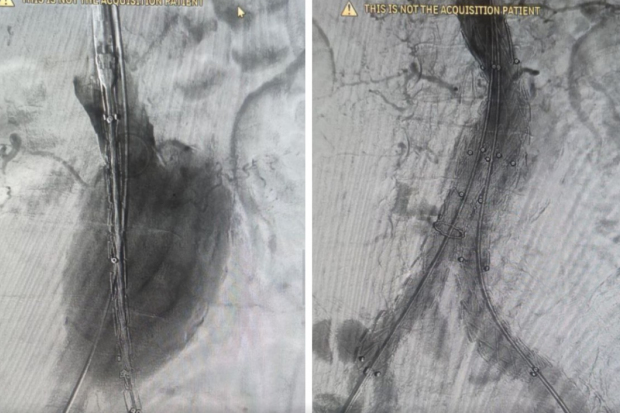

По информации областного комитета здравоохранения, уникальную операцию по установке стент-графта пациенту выполнили врачи волгоградской областной больницы № 1, что подтверждает высокий уровень развития сосудистой хирургии региона.

Решение о проведении малотравматичного вмешательства было принято исходя из крупного размера аневризмы у пациента, симптомов сдавливания окружающих органов, а также возраста пациента старше 70 лет и наличия у него тяжелых хронических заболеваний.

В связи с этим традиционное вмешательство было чрезмерно рискованным. Медики старались свести к минимуму риск разрыва аневризмы, что представляет прямую угрозу для жизни. Для этого и был установлен стент-графт. Он состоит из стента – металлической или полимерной сетки, которая поддерживает стенку сосуда, а также графта – тканевой или синтетической оболочки, обеспечивающей дополнительную прочность и защиту.

Конструкция позволяет укрепить стенку аорты изнутри, создавая новый прочный канал для кровотока. Это помогает восстановить функцию магистрального сосуда и предотвратить жизнеугрожающие осложнения.